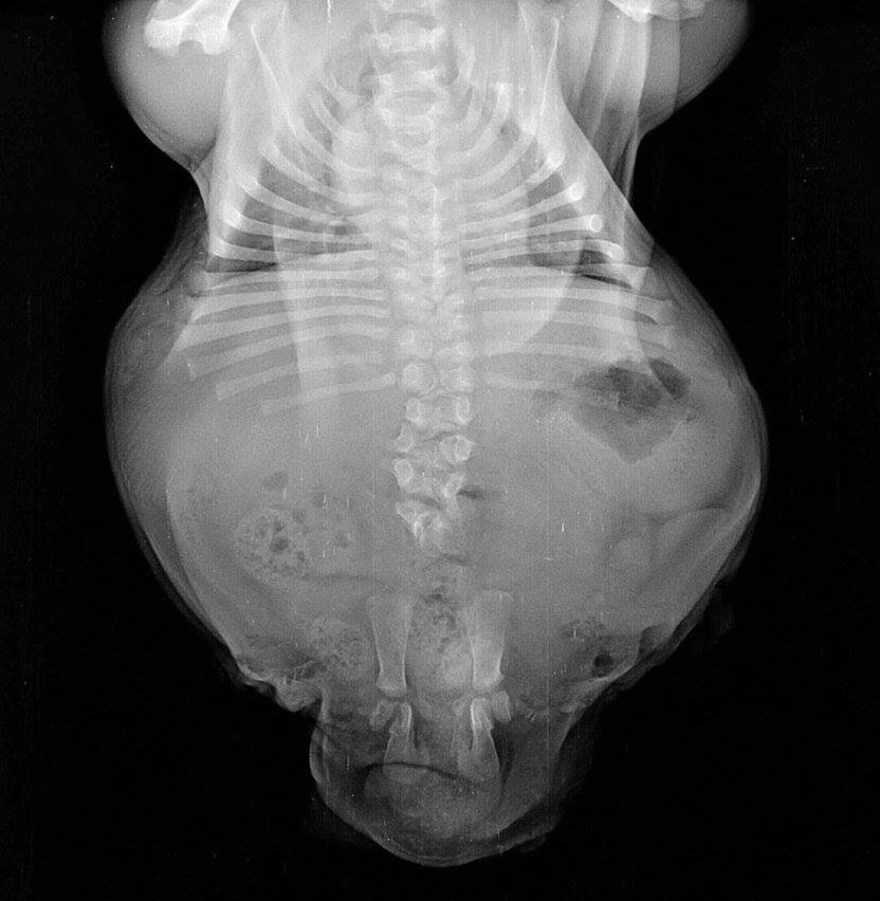

เมื่อเกิดมา พิการ บอนไซแคระสองขาหลังขาด้วนเจ้านายช่วยเหลือ จนตอนนี้แข็งแรง สุขภาพดี มาชมภาพน่ารักๆกัน

Half A Dog, Twice The Love: Rescued Puppy Born With 2 Legs Needs Your Help

Bonsai the Bulldog puppy